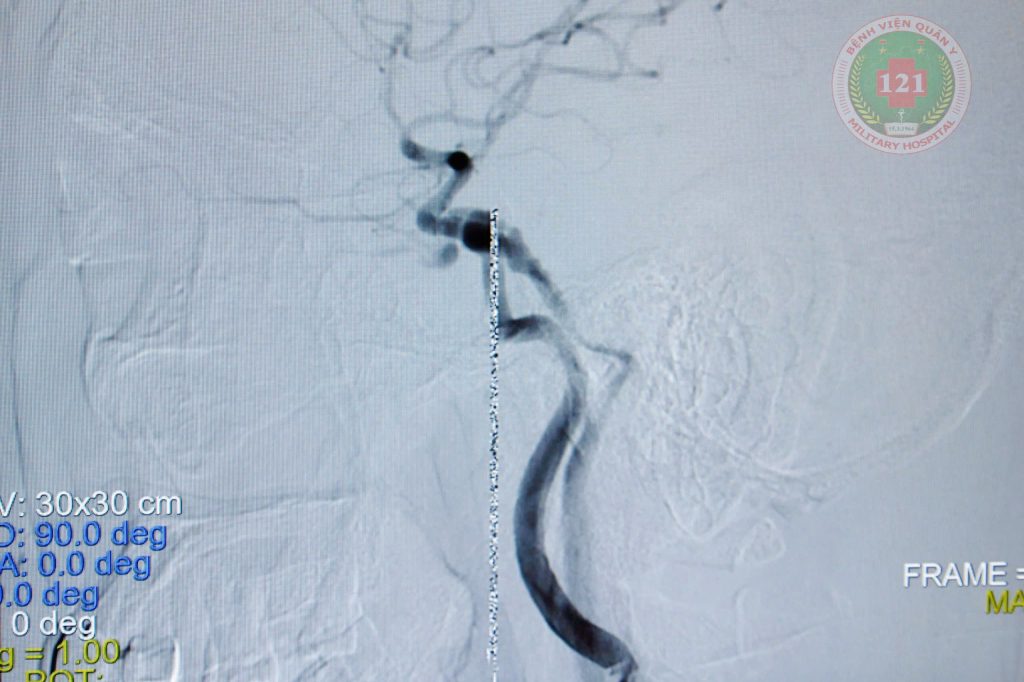

Thông động tĩnh mạch xoang hang trước khi thả coil và sau khi thả coil |